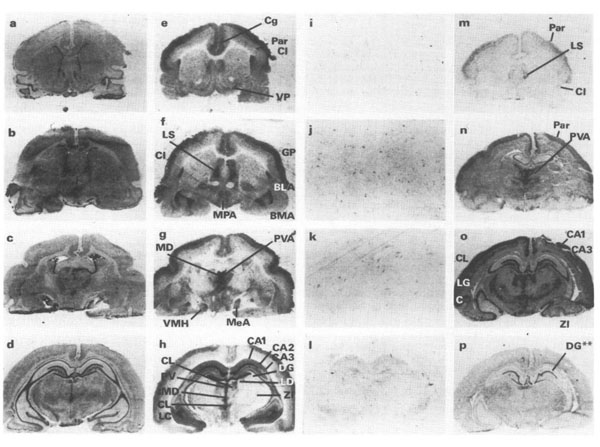

Distribution of 5-ht7 receptor binding and mRNA in guinea-pig coronal forebrain sections dissected form guinea pig brains (p/n GP-T040). (a-d) Histological sections stained with 0.25% Cresyl violet. (e-h) Autoradiographs of total binding from same sections following incubation in 1.0 nm [3HJ-5-carboxamidotryptamine ([3H]-5-CT) in the presence of (-)-cyanopindolol and sumatriptan. (i-I) Autoradiographs from sections adjacent to those in h-n, with non-specific binding defined in the presence of 1μM 5-HT. (m-p) Autoradiographs following in situ hybridization using [35S]-UTP-labelled antisense (m, n, o) and sense (p) strand riboprobes. Darker areas correspond to higher mRNA levels. Section in panel m from a different experiment from n-p. Hybridization in ventromedial hypothalamus is dense just lateral to suprachiasmatic nuclei (arrowhead). Hybridization using sense strand probe was not above background except in hippocampal dentate gyrus (DG**). Abbreviations are defined in Table 2.Figure 5. PMID: 7647964.